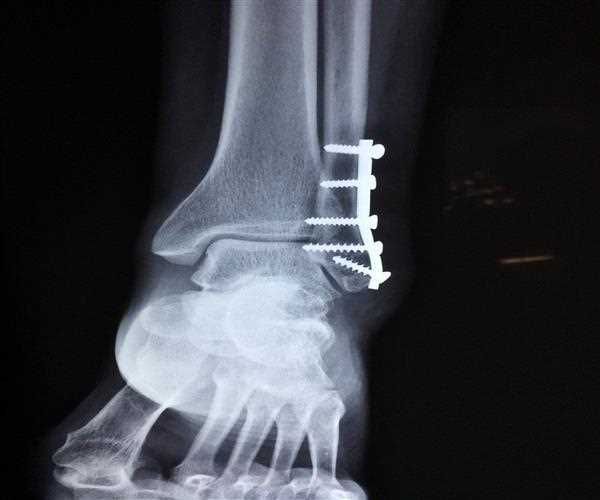

Fracture dislocation: This occurs when a joint becomes dislodged and one of the bones in the joint breaks.

Intra-articular fractures: This occurs when the fracture extends to the joint surface.